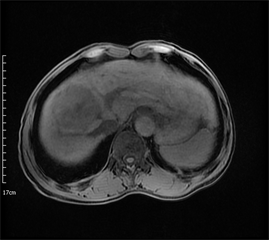

Figure 1. Axial MRI images of HCC patient before TACE treatment. (a) T1-weighted unenhanced image shows a hypointensive lesion in right lobe of liver. (b) Arterial phase contrast-enhanced image shows a heterogeneous enhanceed lesion. (c) ADC map. (d) Dslow map. (e) Dfast map. (f) f map.